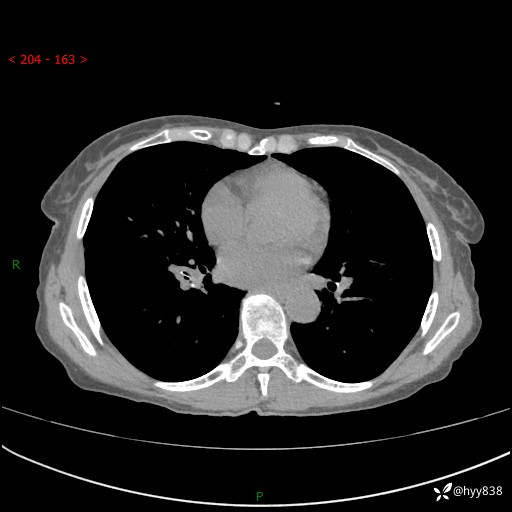

患者性别:男

患者年龄:69岁

简要病史:咳嗽咳痰2月,夜间加重

临床诊断:感染

胸部CT平扫